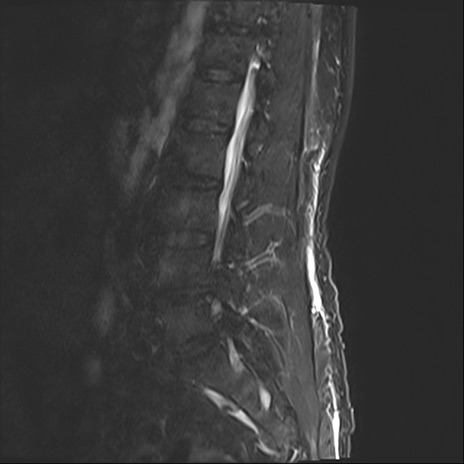

【整形】TIPS症例2 腰椎MRI STIR(矢状断像)

【症例】70歳代男性

【主訴】左下肢痛

【現病歴】2週間前くらいから腰痛、左下肢痛あり。左臀部から大腿、下腿外側のしびれが常時ある。歩行とともに同部位の痛みあり。

【身体所見】Lasegue70-/60+、Bragard-/±、PTR ±/±、ATR -/-、IP 5/5、TA 5/4、TS 5/5、EHL 右第1足趾なし/3、FHL 5/5、hypersthesia(-)、足背動脈触知良好

異常所見と診断は?